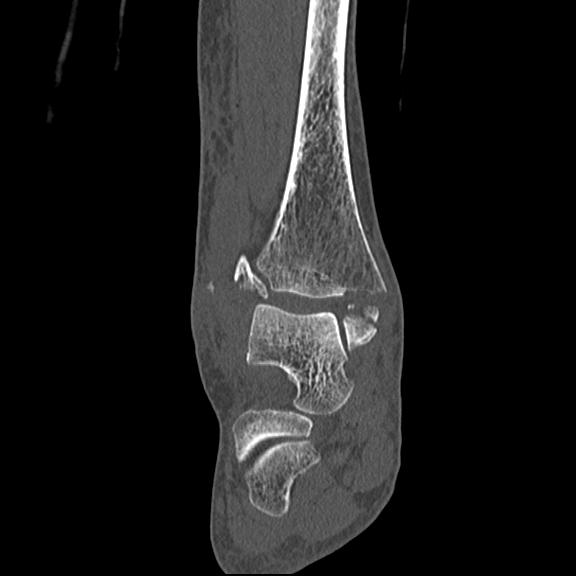

56476 8/28 4R 1/21 2R 左足関節 デジカメ写真 72歳女性 右足関節AS

102755 1/4 2R 1/15 2R 右足関節 68歳女性 右三果脱臼骨折